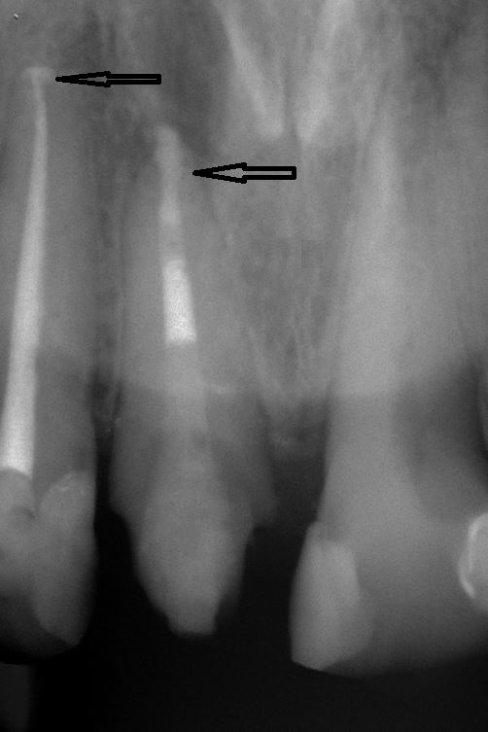

Normalerweise werden Wurzelkanalfüllungen bisher teilweise "nach Gefühl" durchgeführt, da der Zahnarzt den genauen Verlauf der Wurzelkanäle nicht immer eindeutig erkennen kann und kleinere Kanäle oft gar nicht aufzufinden sind.

Durch eine bis zu 24-fache Vergrößerung sind die Kanäle besser darstellbar und dadurch auch effizienter zu reinigen. Durch Reste von Pulpagewebe im Wurzelkanalsystem kann eine Entzündung entstehen, mit der Folge einer erneut notwendigen Wurzelkanalbehandlung oder dem Zahnverlust.

Der Einsatz des Mikroskops ist keine Garantie für den Erfolg einer Wurzelbehandlung , erhöht aber deutlich die Erfolgsquote und führt zu einem vorhersagbarerem Ergebnis.

In Verbindung mit moderner Abfülltechnik , die eine 3-dimensionale Abfüllung der Kanäle ermöglicht, sind bei Ausschöpfung aller Möglichkeiten Erfolge von über 90 % möglich.

Auch bisher häufig als unrettbar eingestufte Zähne sind durch diese aufwendige Techniken häufig zu erhalten.

Fallbeispiel für eine unvollständige Wurzelfüllung

nach Revision und dichtem Verschluss